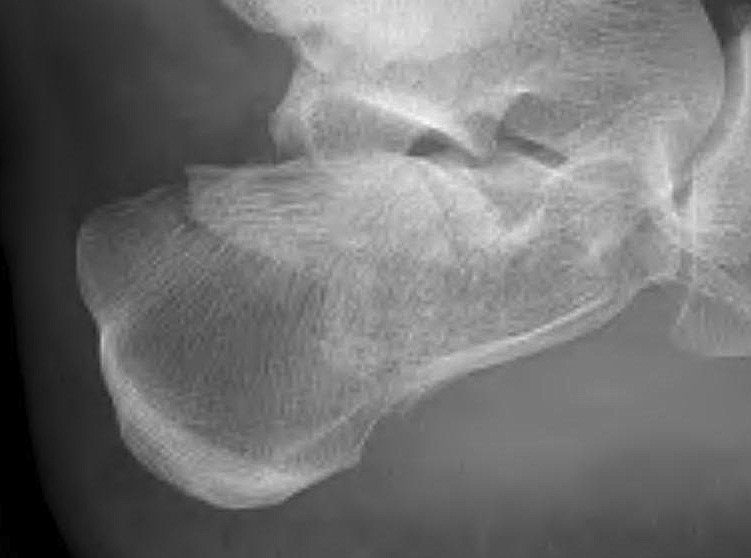

Elevation and Depression Compression fracture on the posterior humeral head at the site where the humeral head impacted the inferior glenoid rim Dutton, 2012. pg. 381 ... Access Full Source